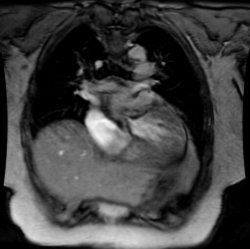

Cine MR of Aortic Stenosis:

The images below are from a cine MR exam of a patient with aortic stenosis. The exam revealed thickened valves with little mobility. There is a thin turbulent jet through the stenotic valve. Post-stenotic dilatation of the ascending aorta could be seen on other images.